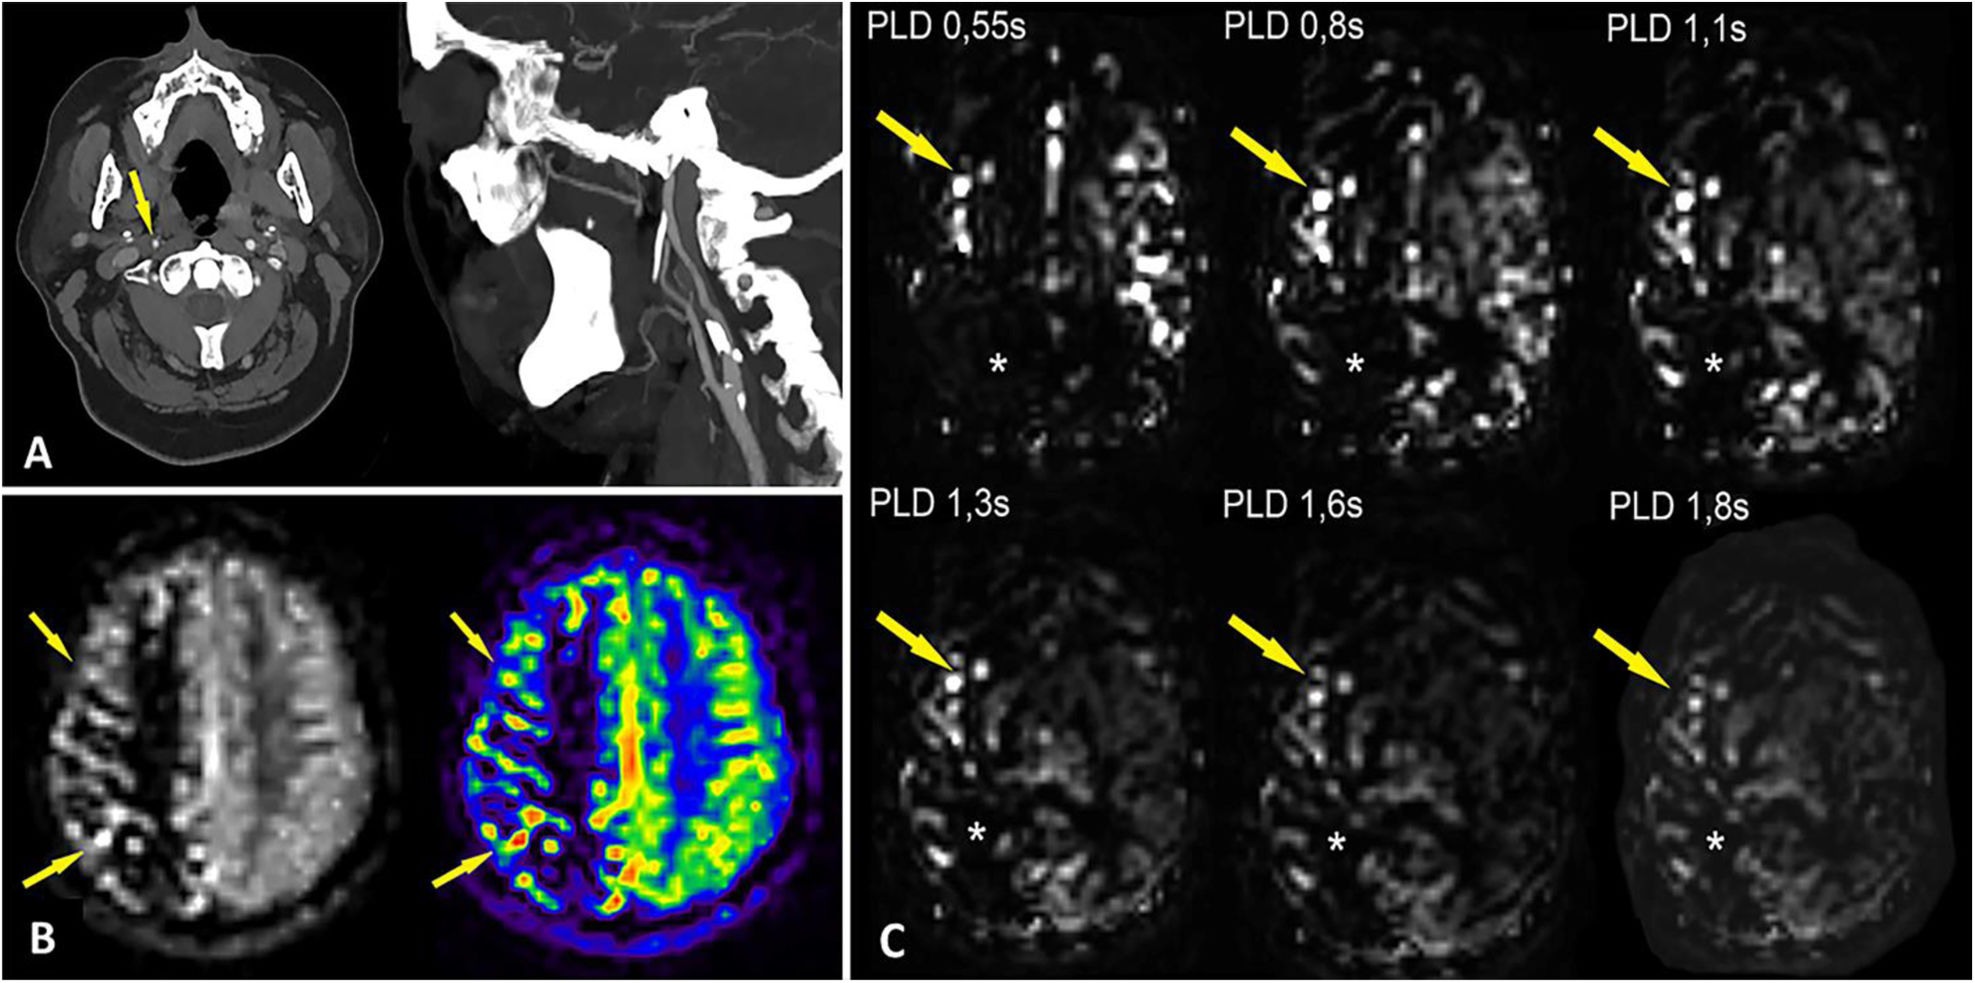

Arterial spin labelling (ASL) is a magnetic resonance imaging perfusion technique used to study cerebral blood flow. It differs from magnetic susceptibility-based perfusion sequences in that it does not require contrast media, but rather uses the signals emitted by pre-labelled protons. It is useful in the exploration of several different kinds of neurological pathologies including ischaemic stroke, brain tumours, dementia and epilepsy. However, it presents numerous artefacts that radiologists must be familiar with to ensure a correct interpretation of findings.